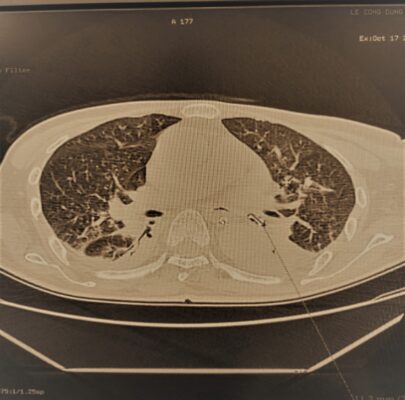

Bệnh nhân nam giới – 60 tuổi, có tiền sử teo não, vào khoa hồi sức trong tình trạng khó thở, suy hô hấp. Bệnh nhân được chỉ định chụp cắt lớp lồng ngực và đã phát hiện trong lòng khí phế quản tại thùy dưới trái bệnh nhân có dị vật.

Dị vật phế quản thùy dưới trái Hình ảnh dị vật sau khi được lấy ra